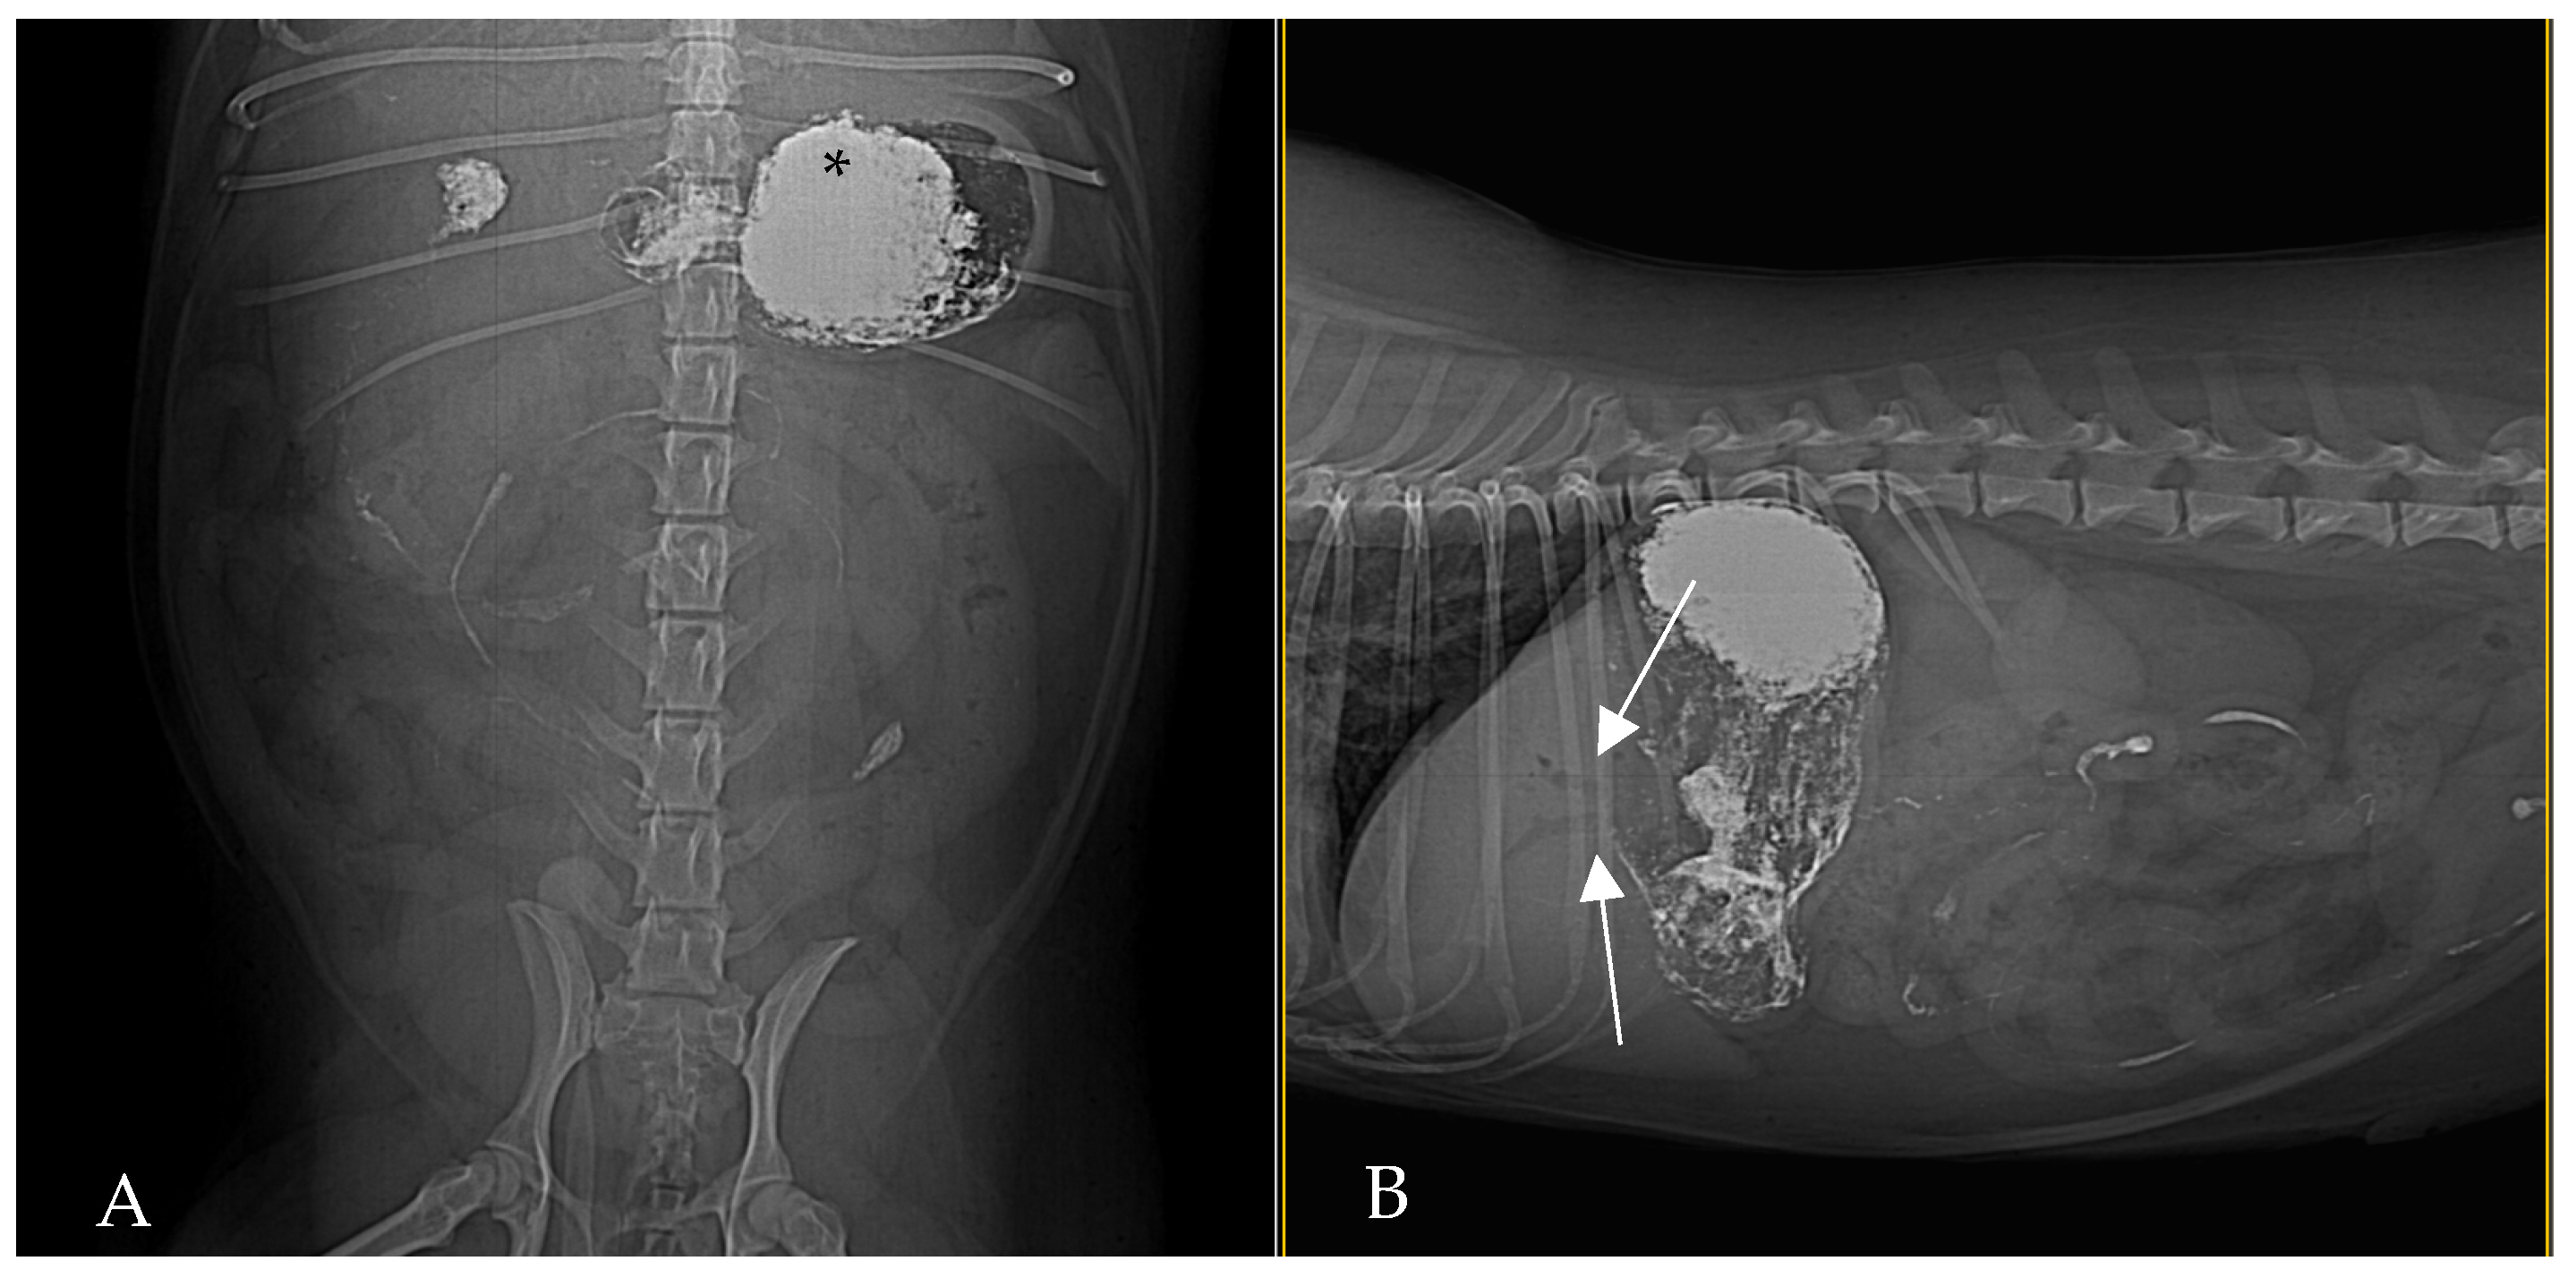

By 2 h post-barium (Figure 3) administration, radiography demonstrated biliary tree and gallbladder had become opacified with barium, indicating retrograde flow of contrast from the duodenum into the biliary ducts. This reflux was even more conspicuous in subsequent images: at 24 h post-contrast, the branching biliary tree was fully outlined by hyperattenuating contrast medium, and the gallbladder lumen was coated with barium. Concurrently, by 24 h a substantial amount of barium had reached the transverse and descending colon, increasing the opacity of the colonic contents. Barium residues cleared gradually over the next 72 h, with most of the contrast eliminated by day 3 (Figure 4).

Figure 4. Right lateral (A) and ventrodorsal (B) abdominal radiographs, 48 h post-barium. Barium contrast is mildly persistent in the biliary tree (arrows), and the contents of the colon show increased opacity due to a large amount of residual barium. Most of the contrast has cleared by this time, except for that in the biliary system and colon.